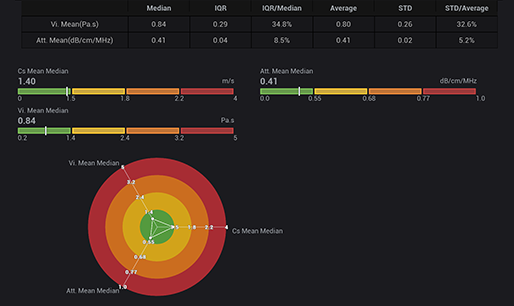

STVi maakt de kwantitatieve evaluatie van weefselviscositeit mogelijk en biedt realtime, multi-parametrische beeldvorming. Dit maakt een bredere benadering mogelijk van beeldvormingsdiagnose en kwantitatieve analyse van chronische leverziekten, borstlaesies en andere aandoeningen.

Dubbele kwantitatieve co?ffici?nten

Beoordeling van chronische leveraandoeningen